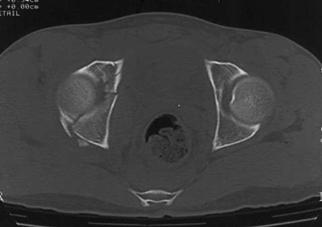

Compresie laterala

Fracturi pelviene multiple Fracturi pelviene multiple

Compresie bilaterala Compresie bilateralaAspect CT

Fracturi pelviene multiple Fracturi bilaterale de ramuri pubiene

Compresie bilaterala Aspect CT Disjunctie sacro-iliaca stanga Compresie antero-posterioara

Cistograma Fracturi ale ambelor

ramuri pubiene

Contur neregulat al vezicii urinare Disjunctie

sacro-iliaca dreapta